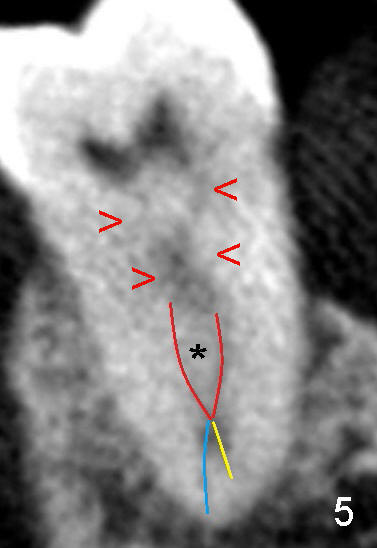

CT近中根断面显示它仍然有两个根管,但是它们非常接近(图四;B:颊侧),由于近中根弯曲(图一至图三),我们必须做多个CT切面(没有用图逐个显示)才能以上结论,不过让我们用图五示意图表明:箭头指向近中两个根管共同部分,两根红线代表这两个根管相对独立部分(它们两者之间有一个峡部(*),但是两者仍有沟通),然后它们在根尖处融合,最后由一个主要分支(蓝线)出去(术中十五号扩大针抵达根尖狭窄处;图五黄线代表小分支),总之,大部分感染牙髓组织被清洗(峡部也被磨掉或者搞通了),根管充填(图六黑色部分),所以术后疼痛消失,但是必须做牙冠防止冠部细菌进入,严密观察。